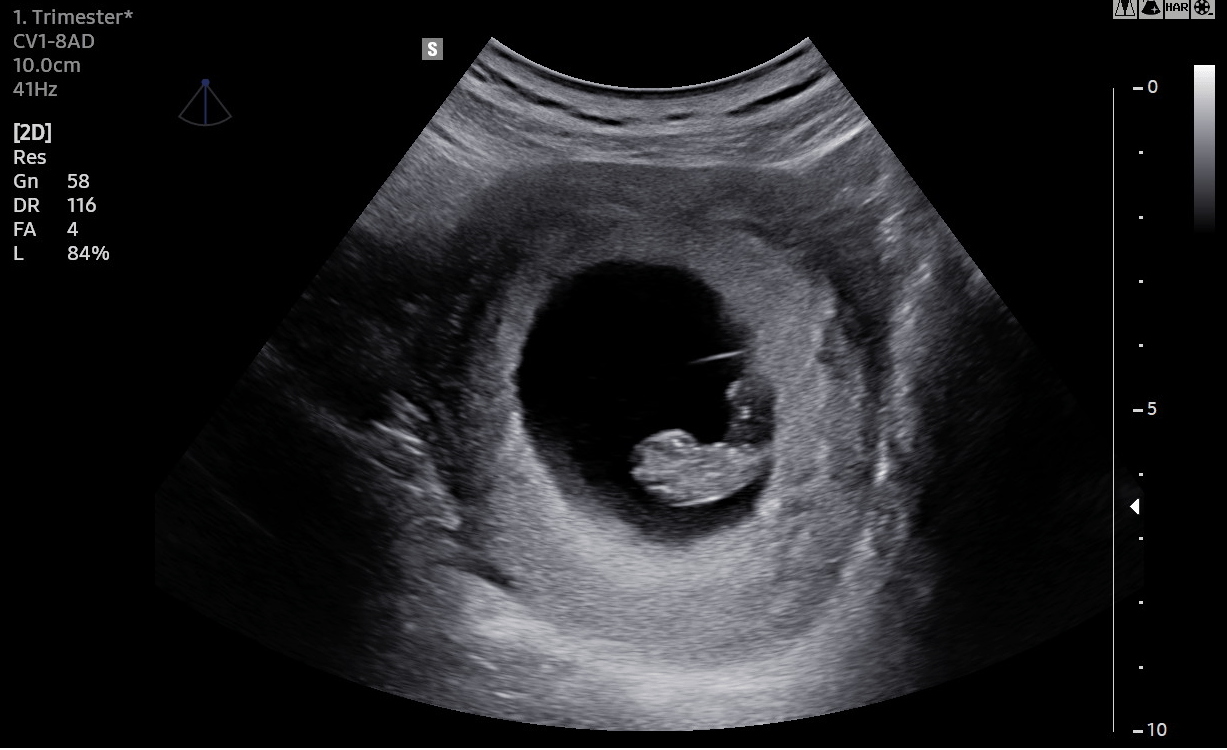

Ultraschall im Rahmen der gesetzlichen Mutterschaftsvorsorge-Richtlinie (Ultraschall I)

Es erfolgt neben der Feststellung des Schwangerschaftsalters und der Anzahl der Embryonen die Kontrolle des Herzschlages. Ein Organscreening ist erst in der 19.-22. SSW vorgesehen (Ultraschall II).